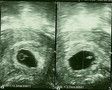

Man sieht wirklich noch gar nichts! Das dicke Ende, also quasi das Siegel am Ring, ist mein Wurm. Noch nicht mal ein Gummibärchen, aber das Herz hat schon geschlagen. In 2 Wochen gibt´s das nächste Bild. FREU!!!